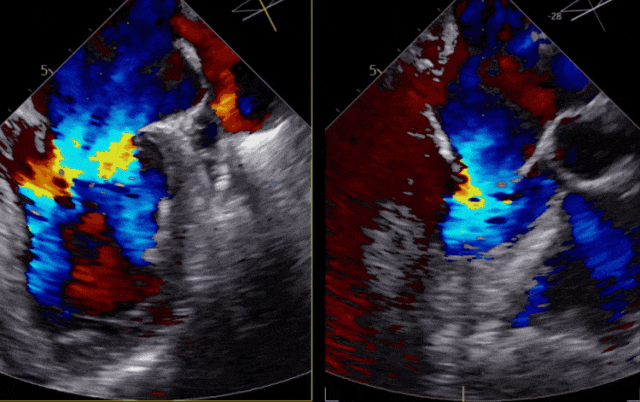

术 中

手术经股静脉置管,房间隔穿刺并置入导引导管后,送入第一枚NTR,经过左房定位到达反流位置,准确捕获并夹合前、后瓣反流严重部位,原本重度的二尖瓣反流降低为中度,决定植入第二枚NTR,最终反流降低至轻度,超声评估夹子夹合稳定、肺静脉逆流改善、平均跨瓣压差3.17mmHg,患者各项生理指标正常,手术顺利完成。

图片

▲患者术后超声影像